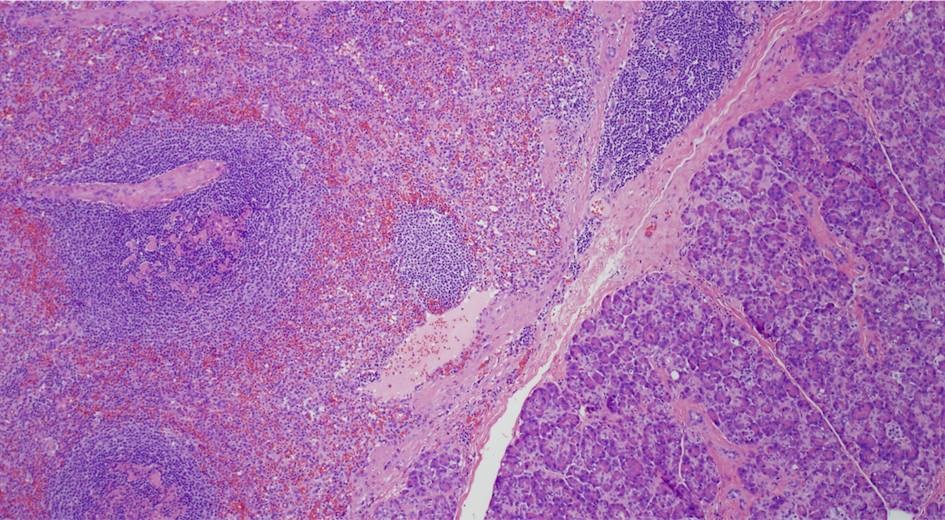

A 32-year-old Hispanic woman presented with recent onset of moderate right upper quadrant abdominal pain. The pain was not associated with any aggravating or relieving factors and gradually resolved during her hospital stay. Past history was significant for obesity and hysterectomy. Physical examination showed normal vital signs and mild upper abdominal discomfort on deep palpation. Comprehensive laboratory work-up was unremarkable. A non-contrast computed tomography (CT) of the abdomen showed a vague lesion in the pancreatic tail. A contrast-enhanced magnetic resonance imaging (MRI), done to better characterize the lesion, showed a 4-cm pancreatic tail mass, and a 1-cm cystic area in that mass (Figure 1). Endoscopic ultrasound (EUS) showed a 4-cm oval, hypo-echoic solid mass in the pancreatic tail, and a 1-cm an-echoic (cystic) area within that mass. Fine needle aspiration of the mass showed well-circumscribed lymphoid aggregates, without monoclonal expansion, mixed with red blood cells. For concerns of malignancy, the patient underwent distal pancreatectomy with splenectomy. The resected specimen showed a well-circumscribed 4-cm red-brown lobulated mass representing ectopic spleen with reactive lymphoid hyperplasia (Figure 2) (Figure 3), and a 0.7-cm multilocular benign squamous cyst within the accessory spleen (Figure 4). Post-operative course was unremarkable and the patient was discharged home in a stable condition.

Figure 3 Low power cross section through the resected specimen shows a benign pancreatic tissue on the right in purple, separated from the lymphoid aggregates or white pulp and red pulp of the accessory spleen on the left.